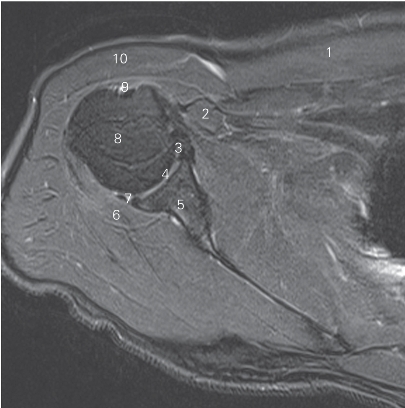

图4-10 经肩关节下份的横断层MR T2WI FS

1 胸大肌 pectoralis major 2 胸小肌 pectoralis minor

3 喙肱肌 coracobrachialis 4 肩胛下肌 subscapularis

5 大圆肌 teres major 6 小圆肌 teres minor

7 关节盂 glenoid cavity 8 冈下肌 infraspinatus

9 肱二头肌长头 long head of biceps brachii

10 三角肌 deltoid